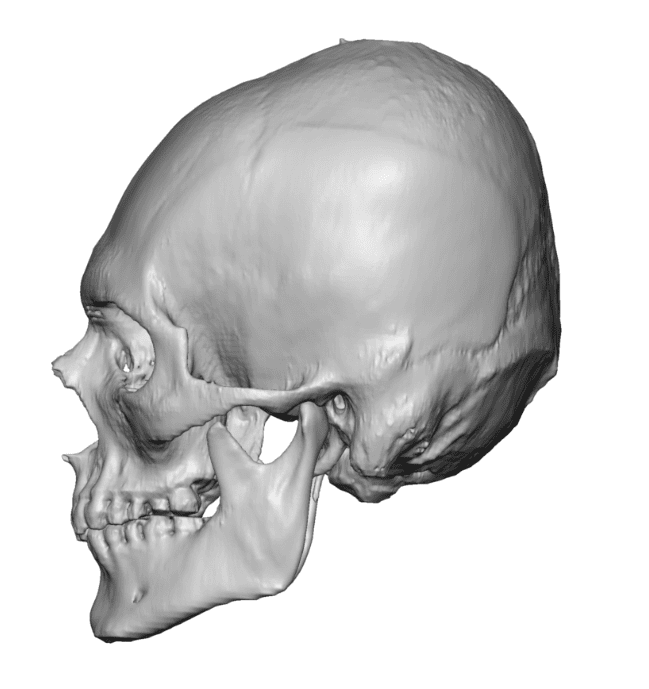

Desire for an improved head shape so that it looks rounder and not so peaked or sloped.

Placement of custom skull implant for parasagittal augmentation to create a rounder head shape. An example of what appears to be a high sagittal crest that is really low parasagittal skull areas.

Desire for an improved head shape so that it looks rounder and not so peaked or sloped.

Placement of custom skull implant for parasagittal augmentation to create a rounder head shape. An example of what appears to be a high sagittal crest that is really low parasagittal skull areas.